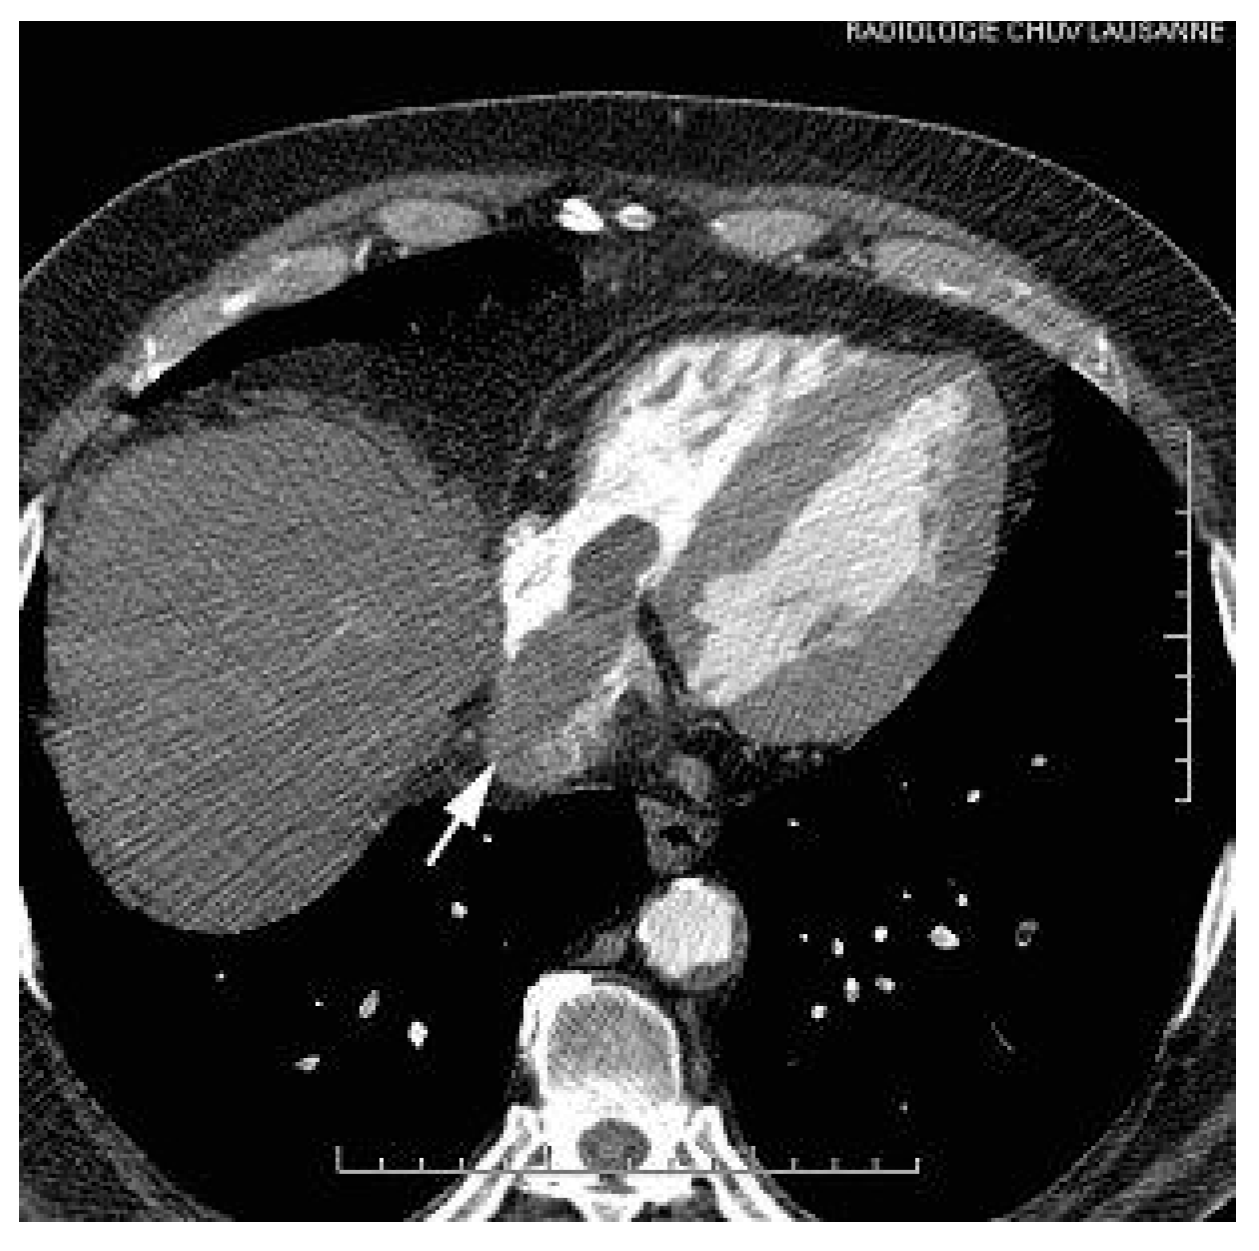

A thoraco-abdominal computed tomography (CT) scan showed the presence of a huge right hepatic mass with extension into the IVC and the RA (Figure 2 and Figure 3).

Figure 3. Abdominal CT. Intracardiac mass into the right atrium with extension into the vena cava (arrow).